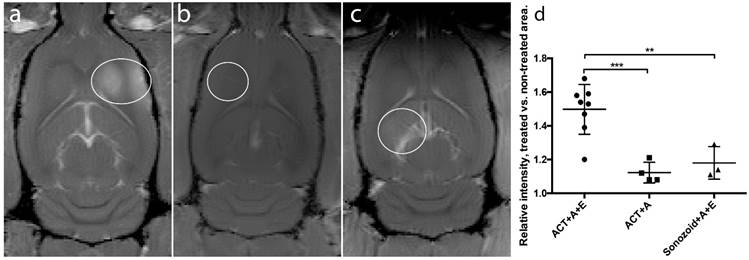

Figure 4

BBBD from a representative animal. (a) Immediately after treatment, (b) 1 day after treatment and (c) 3 days after treatment. (d) Ratio of treated vs non-treated side of the brain, mean and standard deviation from 4 animals.

Recovery of BBBD

The recovery after the BBBD following ACT+A+E procedure was not complete 1 day after treatment (Fig. 4a-c). At this point, the extravasation of gadodiamide revealed a spot like pattern, rather than a diffuse extravasation pattern, which was observed immediately after ultrasound exposure. This pattern was seen in all recovery animals, and can also be seen in animals injected with IRDye 800CW-PEG (Fig. 3). The spots might be a result of the in situ ultrasound beam profile being heterogenous in the sonication focus. Although the beam profile measured in a water thank is homogenous [19], penetrating the skull might generate a more heterogeneous beam profile. This resulted in some areas where the opening was more substantial and consequently prolonged the recovery time. At 3 days' post treatment, a little gadodiamide extravasation into the brain was detectable for some animals, indicating that the BBB was close to or fully recovered. A monoexponential fit (f(t)=0.73·e -0.85t +0.96, R2=0.89) gave a half-life of BBBD recovery of 0.82 days. Previous studies have shown that the BBB closes after 1 to several days [19, 30, 31]. The present recovery kinetics of BBBD are thus similar to those for regular FUS microbubble treatment.